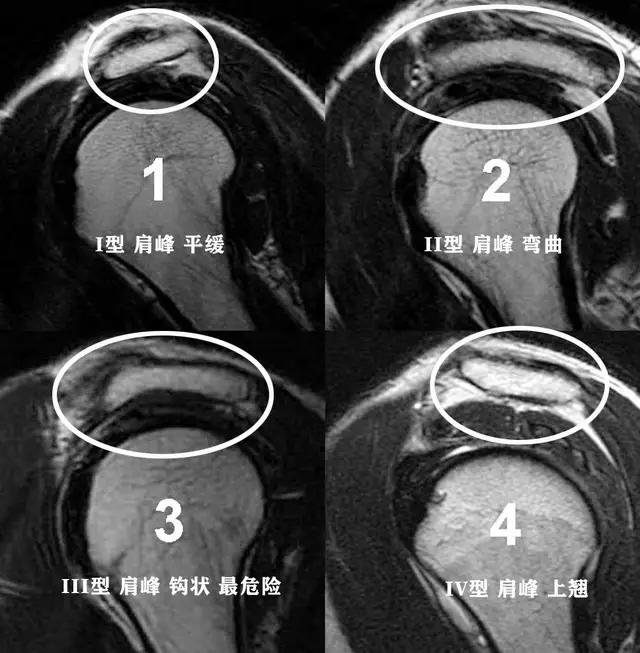

在给大家详细的讲解肩痛之前,大家需要对肩关节的骨骼解剖有一定的认识,我们很多朋友可能知道肩关节的肱骨头、知道肩胛骨,但是很多朋友比较忽视的一个结构就是我们的肩峰,大家在下图可以看到明确的肩峰的位置,其实形象的说,我们可以把肩关节看成是一个小房子,那么肩峰就是房屋的顶棚和房檐儿。

这个房檐形态不是特别的一样,每一个人都有各自的肩峰形态,一般情况下我们的肩峰形态有三种,1种是平的,第2种是略弯曲的,第3种就是钩状的,现在也有人发现有一些人的肩峰是向上翘的,但是这种肩峰不会诱发特殊的症状。主要会导致我们出现肩痛的问题,是三型肩峰,也就是钩状的肩峰,因为向下呈钩状的肩峰,在我们的肩关节活动过程当中,导致肩关节间隙的狭小,会在肩关节活动的过程当中导致撞击!尤其是肩关节做一些前屈、外展、上举的动作时,比如抬起胳膊够比较高的东西,比如羽毛球的挥拍动作。

通常情况下进行肩关节的x线检查或者是核磁检查,可以帮助我们明确肩关节是否存在着肩峰形态的异常以及撞击。

但如果患者经过了保守治疗以后症状仍然特别严重,有可能要进行肩关节镜手术治疗,将钩状的肩峰削平,去除撞击的因素,患者的症状也就会消失了。